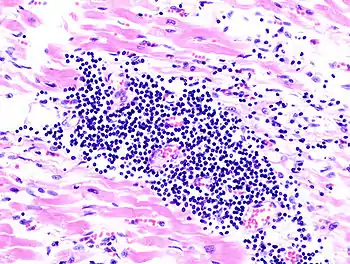

Surgical pathology is the most significant and time-consuming area of practice for most anatomical pathologists. Surgical pathology involves gross and microscopic examination of surgical specimens, as well as biopsies submitted by surgeons and non-surgeons such as general internists, medical subspecialists, dermatologists, and interventional radiologists.

The practice of surgical pathology allows for definitive diagnosis of disease (or lack thereof) in any case where tissue is surgically removed from a patient. This is usually performed by a combination of gross (i.e., macroscopic) and histologic (i.e., microscopic) examination of the tissue, and may involve evaluations of molecular properties of the tissue by immunohistochemistry or other laboratory tests.